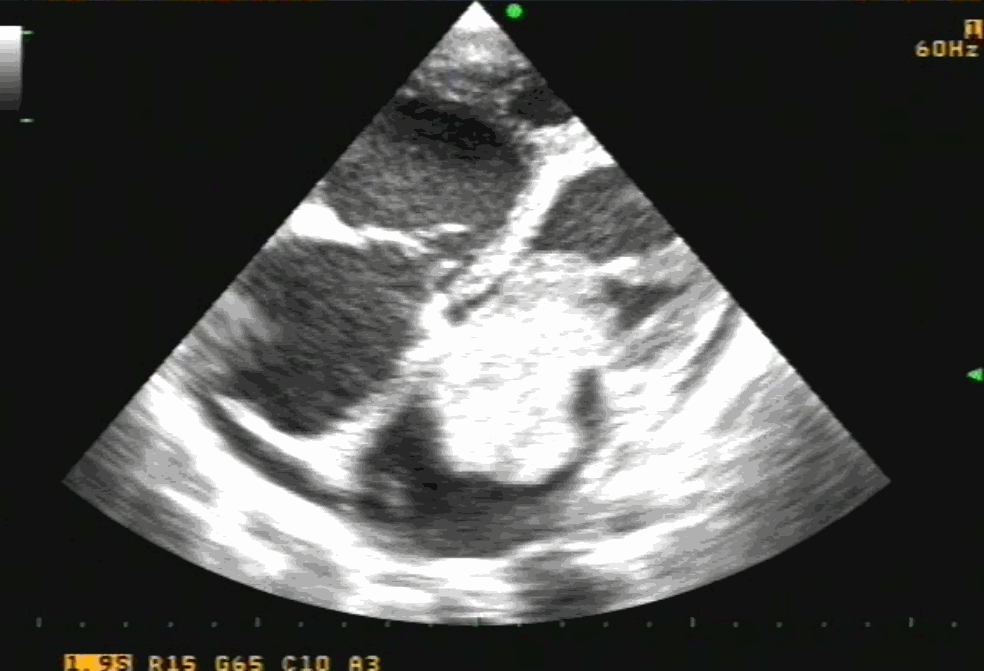

4 chamber view showing what appears to be a small narrow pedicle attaching to IAS. Please note echo imaging can be deceiving. Surgeons must inspect the mass in toto before taking the decision to excise IAS or not

TEE imaging of LA myxoma. Note how fragile the edges of the tumor looks. It explains the high incidence of tumor embolus in this condition. Also, to be noted is the forceful impact of the tumor mass on AML that predisposes chronic mitral valve damage.